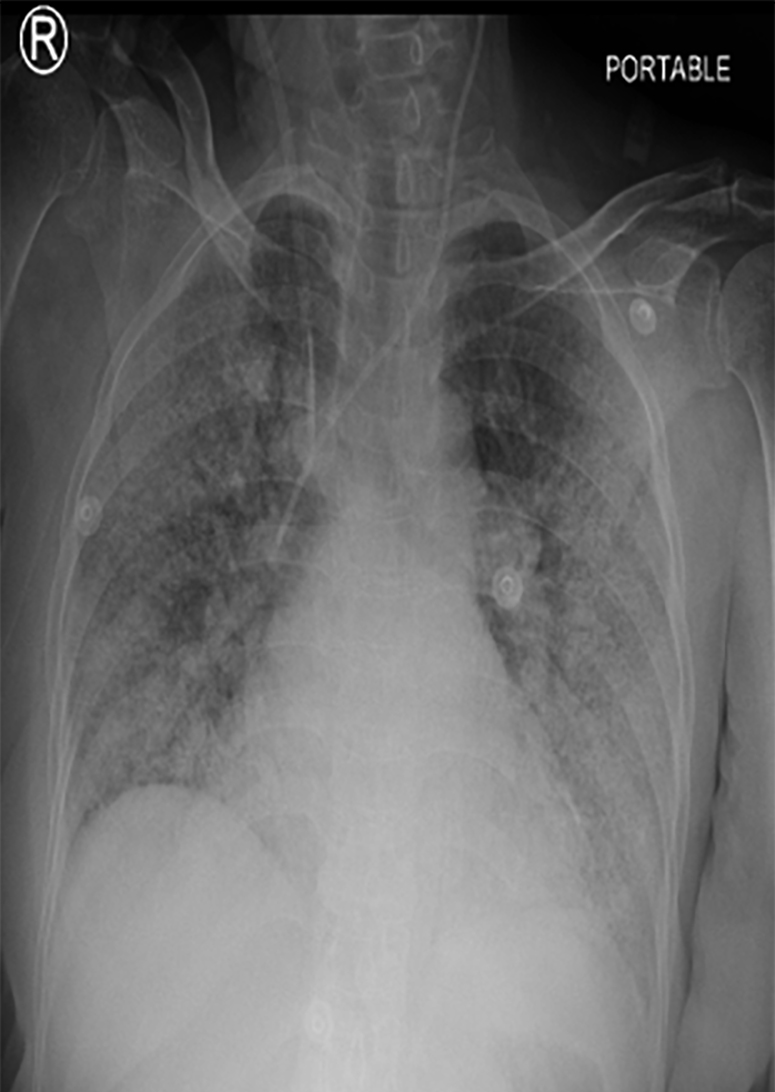

In the COVID-19 ICU, the patient received ceftriaxone, azithromycin, and dexamethasone 10 mg BID. Anticoagulation with low-molecular weight heparin (5000iu BID) was administered. She showed steady recovery throughout her ICU admission. On day nine, coffee-ground material was aspirated through her nasogastric tube despite being on a proton pump inhibitor, so the dose was increased. Her hemoglobin dropped to 8.4 g/dL. On day 11, she was extubated and shifted to the general ward. On the following day, she was again found to have coffee-ground nasogastric aspirate with a continuous drop in her hemoglobin to 6.8 g/dL and received two units of packed red blood cells. A subsequent abdominal computed tomography (CT) scan revealed significant thickening of the stomach wall with specks of air, suggesting a possible sealed perforation or emphysematous gastritis [Figure 2]. As a result, steroids were stopped and her antibiotics were upgraded with the impression of hollow viscous perforation. This was followed by an upper GI endoscopy that showed antral ulcer suspicious for malignancy, for which a biopsy was taken.

Figure 2: A CT showing a significant thickening of stomach wall with specks of air along the stomach, suggestive of a possible sealed perforation or emphysematous gastritis.

On day 20, her condition worsened with white cell count rising to 24 × 109/L, absolute neutrophil count increasing to 22.9 × 109/L, and platelets dropping to 80 × 106/L. A repeat abdominal CT scan showed increased free fluid in the perihepatic area, likely infected, increased abdominal fat stranding, posterior stomach wall showing increased thickness, anterior gastric emphysema, as well as findings of COVID-19 pneumonia [Figure 4]. Despite counseling for surgical intervention, the family refused, and the patient was moved back to the ICU. Her condition deteriorated, leading to a decision not to resuscitate. On day 30, the patient passed away due to ongoing severe septic shock and multi-organ failure. Informed consent was obtained from the patient’s son.

Figure 4: A CT showing significant free fluid in the perihepatic area with increased abdominal fat stranding and gastric emphysema.